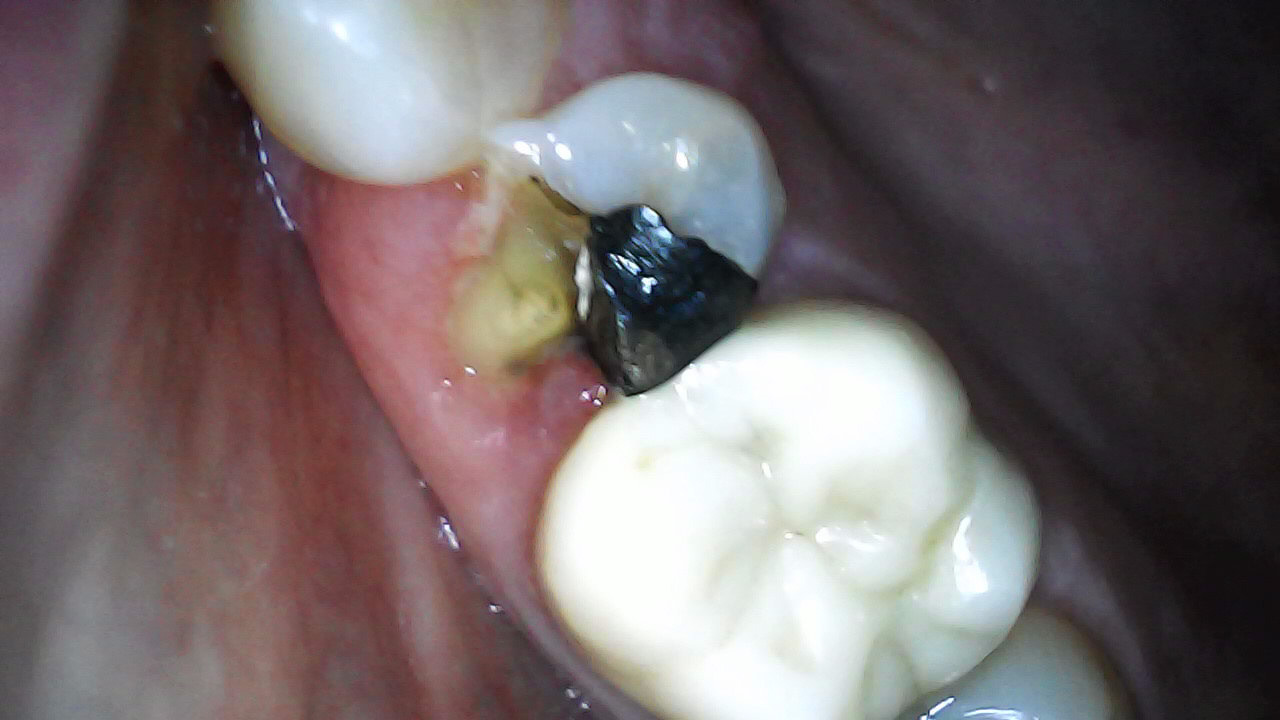

Tooth prep and IDS